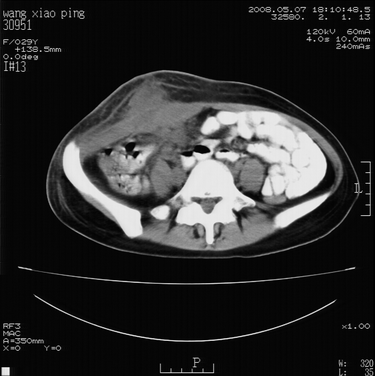

标题: CT13306:F,29,阑尾炎手术后20天,右下腹切口处包块. [打印本页]

标题: CT13306:F,29,阑尾炎手术后20天,右下腹切口处包块.

b超切口疝。

皮肤切口愈合良好。炎性肿块?

肿块密度较低,周围见有条索状影,边界不清,考虑为炎性病变可能大,必要是做增强看看。

支持阑尾术后切口感染。

切口处见液性密度影,周围肌肉肿胀,脂肪层密度增高。

符合术后并发症。